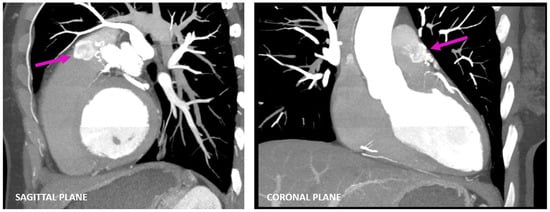

Figure 3. Multiplanar images (sagittal and coronal planes) of coronary CTA acquisitions also visualized using maximum-intensity projection representing a faint flow of contrast from the fistulous connection into the pulmonary trunk—the contrast shunt sign (pink arrow).